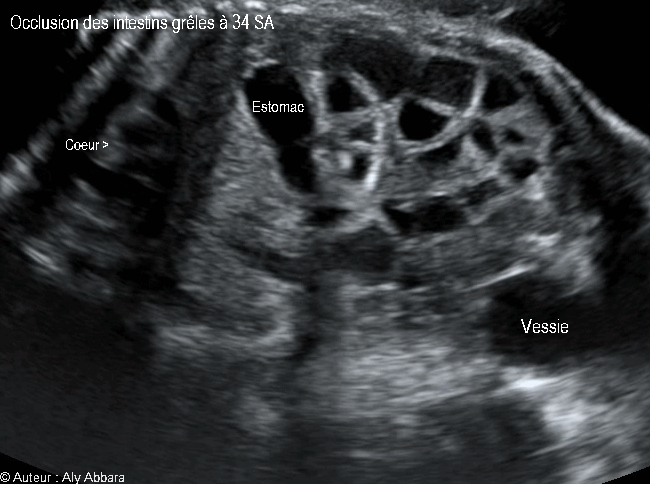

Images échographiques montrant une occlusion intestinale se manifestant par la dilatation des anses grêles et un hyperpéristaltisme.

Cette occlusion intestinale est liée à la présence, dans la fosse iliaque droite, d'un magma d'anses grêles hyperdenses, agglutinées et obstruées.

L'estomac n'est pas dilaté (occlusion digestive basse), mais on note également l’existence de deux anomalies morphologiques associées :

* Une agénésie du rein droit

* L'absence, au niveau de crosse de l'aorte, de sa 3ème branche, c'est-à-dire l'artère subclavière gauche.

Il s'agit d'une fœtus de 34 SA ; après sa naissance à 38 SA, cette occlusion des anses grêles a nécessité deux interventions chirurgicales digestives dans la période néonatale.